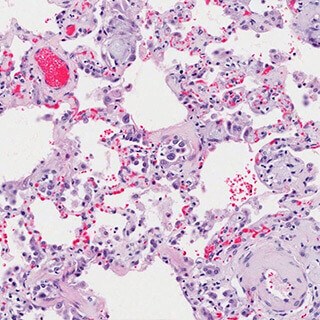

Lobular Carcinoma in Situ (LCIS)

Lobular Carcinoma in Situ (LCIS) is the presence of abnormal cells that form in the milk-producing lobules. LCIS is not cancer, but it is an indication that you have an increased risk of developing invasive cancer.

Because LCIS cells are confined within the lobules, it is not life-threatening. If diagnosed, you have time to thoroughly research treatment options before making a decision. It is very important to complete treatment, however, because women with LCIS have a higher risk of developing invasive breast cancer in either or both breasts.

Invasive/Infiltrating Lobular Carcinoma (ILC)

Invasive lobular carcinoma (ILC) develops in the milk-producing lobules of the breast and spreads to the surrounding breast tissue. It can also spread to more distant parts of the body.